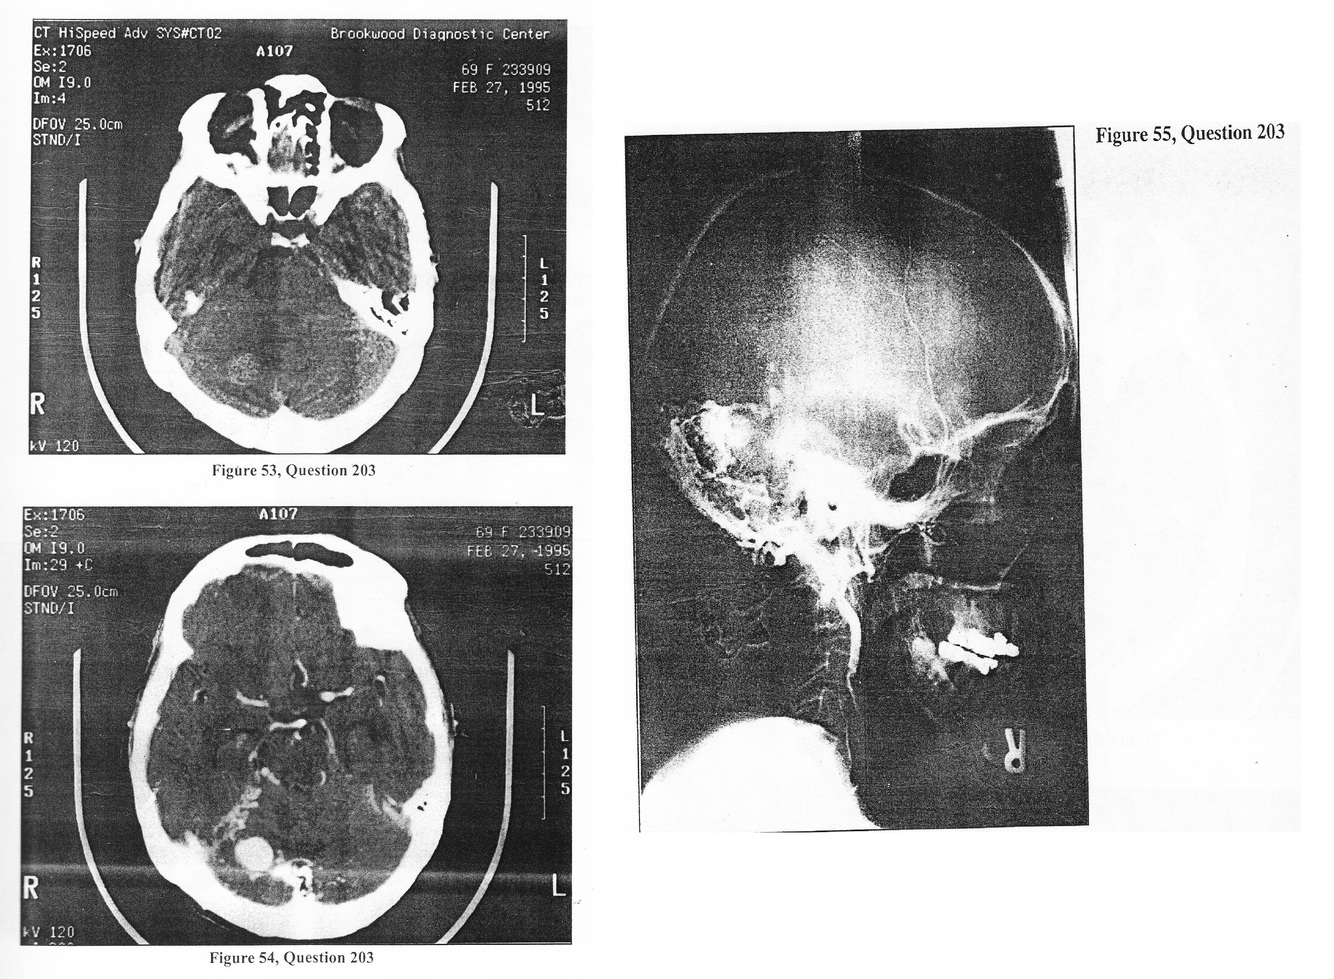

A 69-year-old right-handed female was in her usual state of health until awakening this morning with the worst headache of her life, along with a stiff neck. There had been some numbness and tingling of her arms, however, that has resolved. She presently complains of nausea without vomiting and states she has been diagnosed as having Sturge-Weber syndrome. She has never experienced any episode suggesting a seizure. Examination reveals an anxious and alert woman. Behind her right ear, there is a skin vascular anomaly which blanches slightly when depressed with the finger. There is no papilledema, and her neurologic examination is entirely normal. There is no meningismus. Her initial diagnostic management included a CT with and without contrast (Figures 53 and 54) and a lumbar puncture which was blood tinged and did not clear between tubes 1 and 4. Following admission to the hospital, an MRI and cerebral angiogram were obtained (Figure 55). 203. What is the MOST LIKELY etiology of the patient’s subarachnoid hemorrhage?

A. ruptured cerebral aneurysm

B vasculitis

C. cerebral AVM

D. duralAVM

A 69-year-old right-handed female was in her usual state of health until awakening this morning with the worst headache of her life, along with a stiff neck. There had been some numbness and tingling of her arms, however, that has resolved. She presently complains of nausea without vomiting and states she has been diagnosed as having Sturge-Weber syndrome. She has never experienced any episode suggesting a seizure. Examination reveals an anxious and alert woman. Behind her right ear, there is a skin vascular anomaly which blanches slightly when depressed with the finger. There is no papilledema, and her neurologic examination is entirely normal. There is no meningismus. Her initial diagnostic management included a CT with and without contrast (Figures 53 and 54) and a lumbar puncture which was blood tinged and did not clear between tubes 1 and 4. Following admission to the hospital, an MRI and cerebral angiogram were obtained (Figure 55).

A. 0-5%

B. 10-15%

C. 33-50%

D. >50%